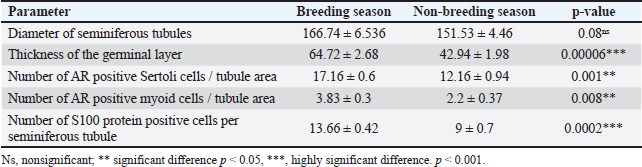

Fig. 2. Photomicrograph of H and E stained section of ram testis during breeding season (a and b) and ram testis during non-breeding season (c and d); showing seminiferous tubules “T”, spermatogonium “SP”, primary spermatocytes “Pr”, and sertoli cells “S”. Morphometrical analysis of seminiferous tubule diameters and germinal layer thickness (e and f). Data are presented as mean ± SE. Ns, non-significant; *** highly significant p < 0.001. Histomorphometry revealed a highly significant difference (p < 0.001) in the germinal epithelium thickness between the breeding and non-breeding seasons. The interstitial tissue among the seminiferous tubules contains loose connective tissue and interstitial Leydig cells (Table 5). Table 5. Histomorphometry measurements representing the mean ± SE of seminiferous tubule diameter, germinal layer thickness, number of AR-positive Sertoli cells/tubule area, number of AR-positive myoid cells/tubule area, and number of S100 protein-positive cells per seminiferous tubule.